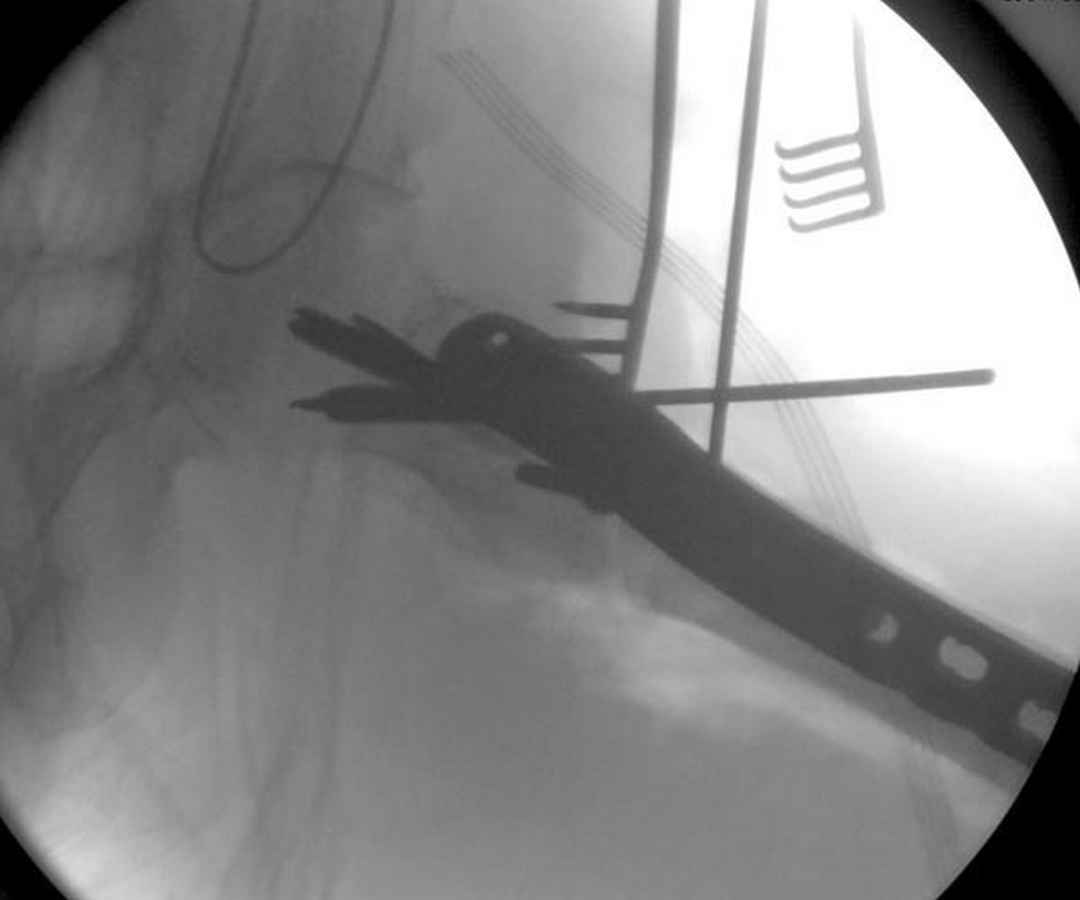

Здесь пара случаев фиксации похожих переломов:

первый высокоэнергетическая травма 36 лет

Djoldas Kuldjanov, M.D.

Department of Orthopedic Surgery

St. Louis University